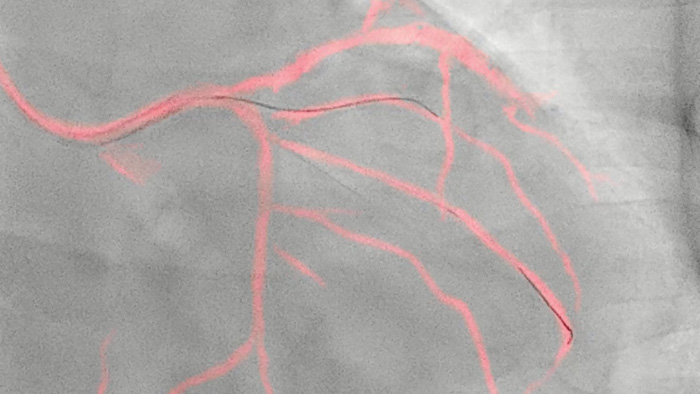

Una tecnología exclusiva de Philips, crea una vista en tiempo real de las arterias coronarias compensada por el movimiento. Un angiograma coronario resaltado se superpone sobre una imagen fluoroscópica 2D en vivo, y crea una hoja de ruta coloreada que se ajusta automáticamente, proporciona retroalimentación visual continua sobre el posicionamiento de cables y catéteres.